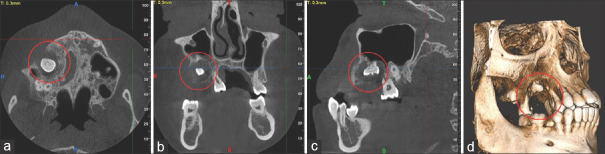

Rosai-Dorfman病(RDD)是一种罕见的组织细胞疾病,典型表现为广泛的淋巴结病变。我们提出一个独特的病例结外RDD在一个14岁的单发上颌病变和轻度双侧下颌下淋巴结病。临床、放射学和组织病理学评估证实了RDD,强调了综合治疗的重要性。免疫组织化学,包括CD68、CD45、cd1a和S100,在诊断中起着至关重要的作用。鉴别诊断包括朗格汉斯细胞组织细胞增多症、厄德海姆-切斯特病、淋巴瘤和组织细胞肉瘤,需要仔细的评估。由于骨受累,手术切除,6个月后成功愈合。我们的病例强调了多学科和科学方法对准确诊断和管理RDD的重要性,特别是在非典型口腔内表现。

Rosai-Dorfman disease (RDD), a rare histiocytic disorder, typically manifests as widespread lymphadenopathy. We present a unique case of extranodal RDD in a 14-year-old with a solitary maxillary lesion and mild bilateral submandibular lymphadenopathy. Clinical, radiological, and histopathological assessments confirmed RDD, highlighting the importance of a comprehensive approach. Immunohistochemistry, including CD68, CD45, CD 1a, and S100, played a crucial role in diagnosis. Differential diagnoses encompassed Langerhans cell histiocytosis, Erdheim-Chester disease, lymphomas, and histiocytic sarcoma, necessitating meticulous evaluation. Surgical excision was performed due to bone involvement, leading to successful healing in six months. Our case underscores the significance of a multidisciplinary and scientific approach for accurate RDD diagnosis and management, especially in atypical intraoral presentations.